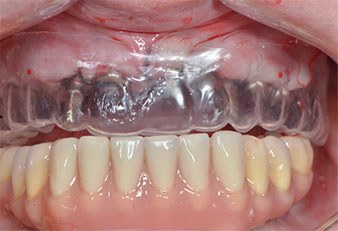

Plantilla de plástico

Fig. 9: Una plantilla de plástico mostró que había suficiente espacio para que la prótesis existente sirviera como prótesis temporal sujeta en los implantes provisionales.